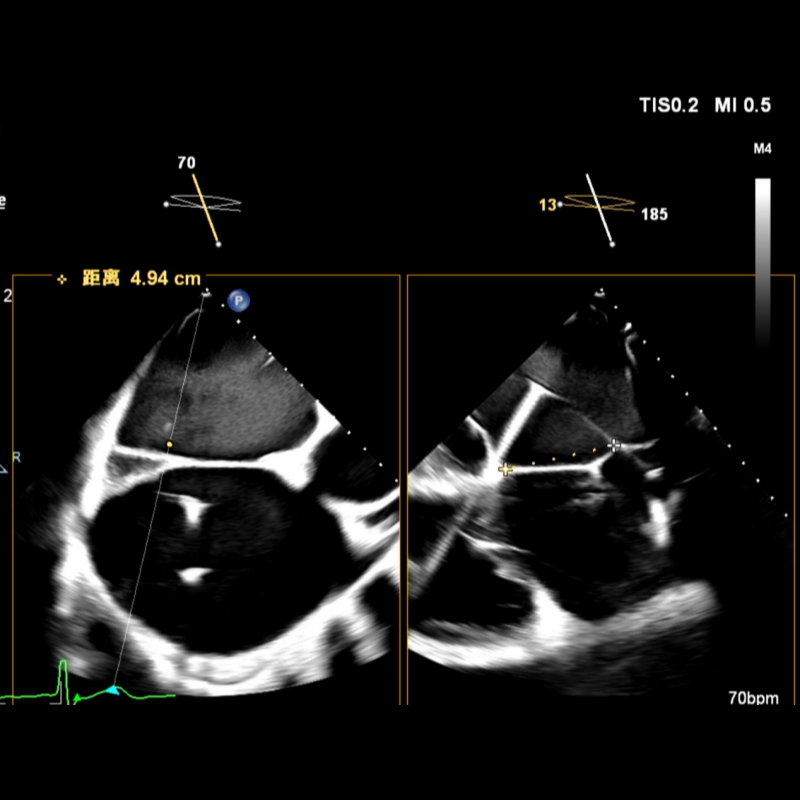

随后更换为可调弯房间隔穿刺鞘,在较定位导丝更靠前、靠下的位置进行穿刺,最终穿刺高度降至4.94cm。因患者房间隔组织异常坚韧,穿刺鞘多次尝试均未能通过,遂使用6mm外周球囊对穿刺部位进行扩张,撤处出原留置在左房内的定位导丝,随后顺利置入SGC。

最终房间隔穿刺高度